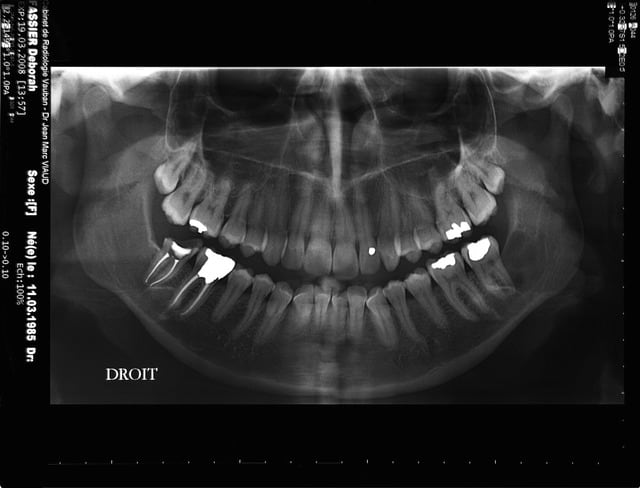

> je viens de mieux regarder la pano de 2008

>

> tu connais la date précise de l'avulsion de la 38

à priori 31/03/2006 pas si vieux que ça je croyais que c'etait 2004, donc évolution rapide

La 37 est impérativement à extraire dans ce cas, faut pas faire de la dentelle car à terme si le kyste récidive et grossit c'est l'intégrité de la mandibule qui est compromise.

A priori vu l'évolution sur les radios et l'âge de la patiente je pense qu'il s'agit d'un kératokyste en première intention.

Mais dans ce cas comme la lésion est encore moyennement étendue je pense que la meilleure option est l'éxérèse plus curetage appuyé de l'os et extraction de la 37 dans la séance => 1 seule puis suivi à 3, 6 12 mois avec OTP.